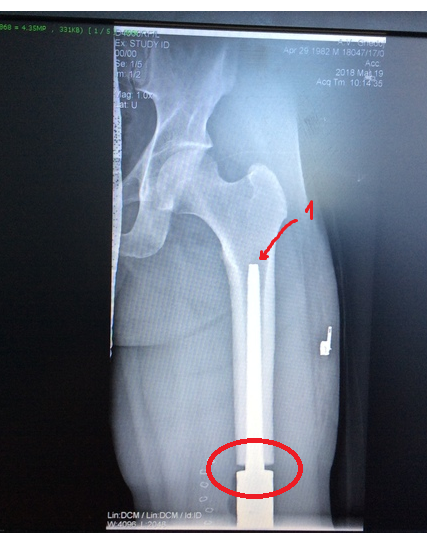

Видел как-то пост про протезирование бедренной кости.( в комментах ссылку дам) Там фотки ещё скидывал, отвечал на вопросы. Напишу про своё.Сегодня ровно год, как хожу с эндопротезом.

В психологическом плане такое довольно сложно принять. Но!!! Когда все доктора говорят, что у меня онкология, встаёт вопрос о собственной жизни, о её сохранении... ампутация/сохранение ноги было соотношение 9/1. Остеосаркома- вещь хреновая, только резекция , химиотерапия не помогает, только приостанавливает рост раковых клеток и метастаз. Главное- чётко соблюдать рекомендации онколога. Сейчас хожу без палки, метастаз нет( на кт показало) . Врач сказал, что нехер организм травмировать кт. Сейчас раз в 3 месяца только рентген. Хочу отдельно поблагодарить Богдаева Юрия Михайловича и Белякова Сергея Васильевича за то, что спасли мою ногу... хотя 7 марта я был у них один на операции... могли бы ампутировать за час и пойти бухать , но они меня чинили около 10 часов...